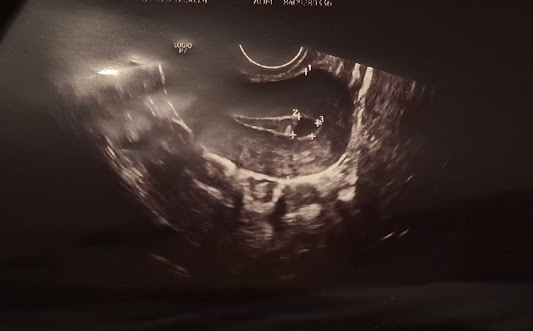

-  в 5+3/5+4 трябва да се вижда вътрематочна бременност. Аз на последните снимки не виждам нищо такова. Така изглеждаше моята двуплоднна бременност в 5+3. Не можеш да го сбъркаш:

Скрит текст: